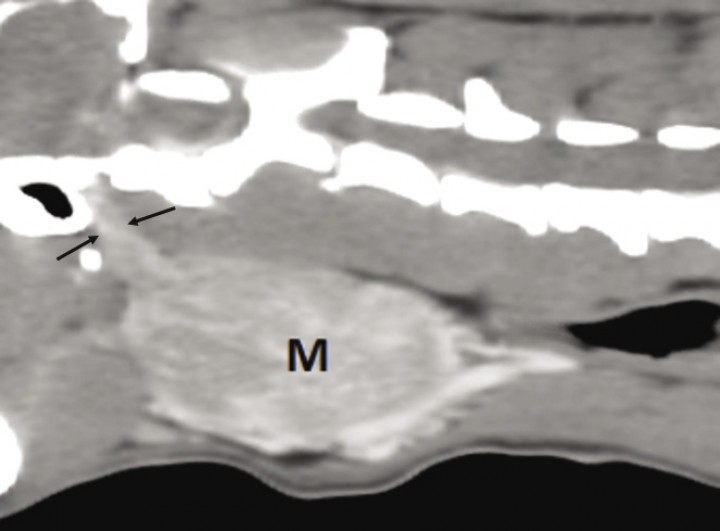

<p>Sección sagital oblicua en ventana de tejido blando poscontraste. Nótese la extensión de la masa (M) hacia la base del cráneo (entre flechas).</p>

Figura 3

Sección sagital oblicua en ventana de tejido blando poscontraste. Nótese la extensión de la masa (M) hacia la base del cráneo (entre flechas).

En la TC se identifica la presencia de una masa cervical izquierda (3 cm de alto x 4 cm de ancho x 5,3 cm de largo), originada en el área de la carótida común izquierda y vena yugular interna a la altura de C3-C4 (Figs. 1 y 2A). Las tiroides resultan dentro de la normalidad. En el estudio poscontraste la masa realza de manera marcada y heterogénea. En su extensión dorsolateral, la masa se extiende hacia la porción dorsal, sobre todo izquierda, de laringofaringe y esófago craneal, causando efecto masa desplazando a la derecha la laringe y aparato hioideo, y ventrolateralmente a la derecha el esófago craneal (Figs. 2B y C). También desplaza dorsolateralmente a la izquierda la musculatura cervical hipoaxial, y la porción más rostral en el lado izquierdo se extiende dorsalmente hacia la base del cráneo, pero no se detecta infiltración intracraneal ni signos de lisis ósea en la base del cráneo (Fig. 3). Aunque la masa parezca bastante bien definida no se puede descartar una afectación de la laringe/laringofaringe y de la musculatura cervical. Se visualiza también una congestión venosa y arterial regional (arteria carótida común y vena yugular interna izquierdas) secundarias a la masa, y aunque no se detectan signos de trombosis u oclusión, no se puede descartar una invasión vascular de estos vasos que están envueltos por la masa.